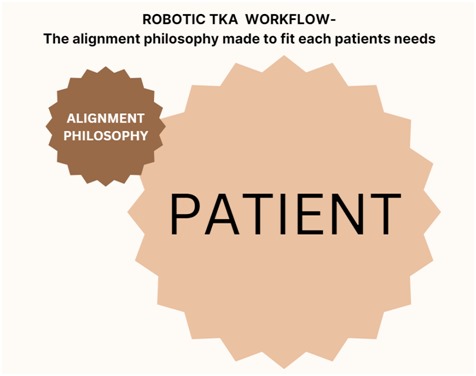

Robotic knee helps us to customize the alignment to the patient and not the patient to the alignment. The advantages of robotic knee is again Customization to patient needs, accuracy of the bone cuts, better ligament balancing and intraoperative immediate feedback for correction and modulation of the process for better outcomes.

The principle of robotic TKA is to move patients towards better alignment but retaining the patient in the same CPAK category so that there is improvement in the patient’s functional outcome and satisfaction rates. This approach is to ensure that “One size fits all” approach is not undertaken and truly individualizing the care to each patient’s needs. This technique and philosophy were advocated by Dr. Johan Bellemens group in 2021 and now evidence is emerging that the CPAK philosophy helps patient achieve better satisfaction rates and our experience of more than 100 robotic knees are pointing towards the same outcome.